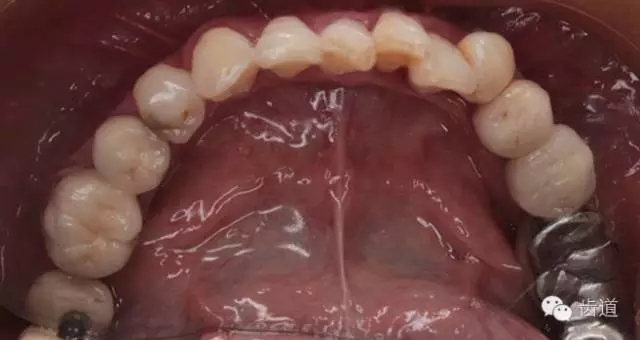

17-12,24-25烤瓷橋修復(fù),邊緣密合可,探-,叩-,松-。

2、上頜牙合面觀